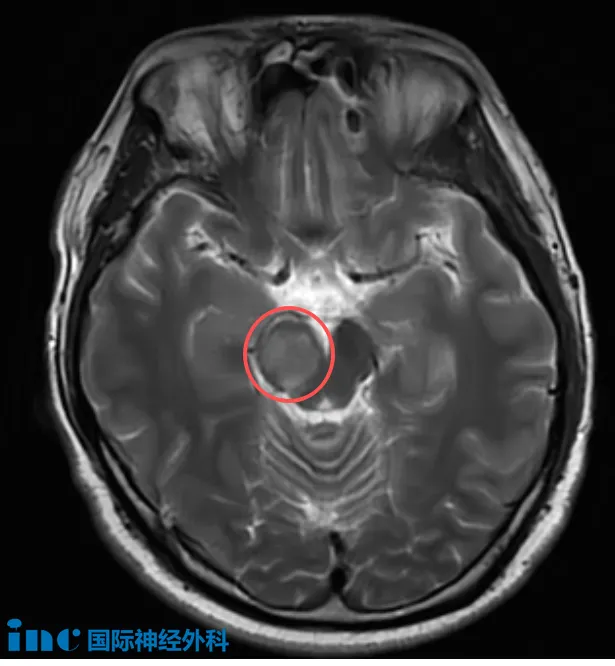

31岁的吴先生正处于事业黄金期,2025年8月下旬因突发头晕与耳闷,检查发现右侧中脑存在病变,自此开始与位于“生命中枢”的未知病变共存。当地医院初步怀疑肿瘤可能性大,随后其症状于9月初消失,医生建议继续观察。为寻求明确诊断,一家人前往北京就医,得到“考虑脑干胶质瘤,可手术治疗”的答复。

“可以手术”本是一线希望,却让家庭陷入更深煎熬。因从发现至今,吴先生表面与常人无异,仅偶有困倦与打哈欠的表现。与其他脑干患者家庭一样,他们不得不面对最令人担忧的假设:

在决策的关键阶段,他们联系到巴特朗菲教授。此刻,他们迫切需要了解:这位国际脑干手术专家能否为他们完成这台“禁区”手术?

“这不是一台简单的手术,若以1至10分衡量难度,我评为7分。它虽非最复杂,但确实比常规手术更具挑战。关键在于尽可能实现广泛切除的同时,保留患者的运动与感觉功能,达成切除与功能保护之间的平衡。这并不容易,但过去40多年我持续学习与实践,正是为了掌握这种技术。我已成功完成大量类似手术,正因如此,我对本次手术充满信心!”这是巴教授基于数十年脑干手术经验的坚定回应。